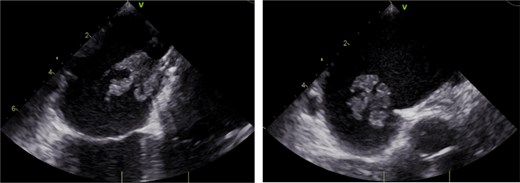

Patient was brought to the operating room, induced, and started on cardiopulmonary bypass following a median sternotomy and adequate aortic/bicaval cannulation. The Gore device was then accessed via an oblique right atriotomy. Under TEE guidance, the Gore device, along with the surrounding atrial septum, was excised (Fig. 2). Purulent material was seen inside the explanted vegetation. A portion of the patient’s pericardium was then harvested and used for patch repair of the large atrial septal defect that remained following explanation. The pericardial patch was anchored with running Prolene.

The surgical explanted Gore Cardioform Septal Occluder with surrounding infected atrial septum.